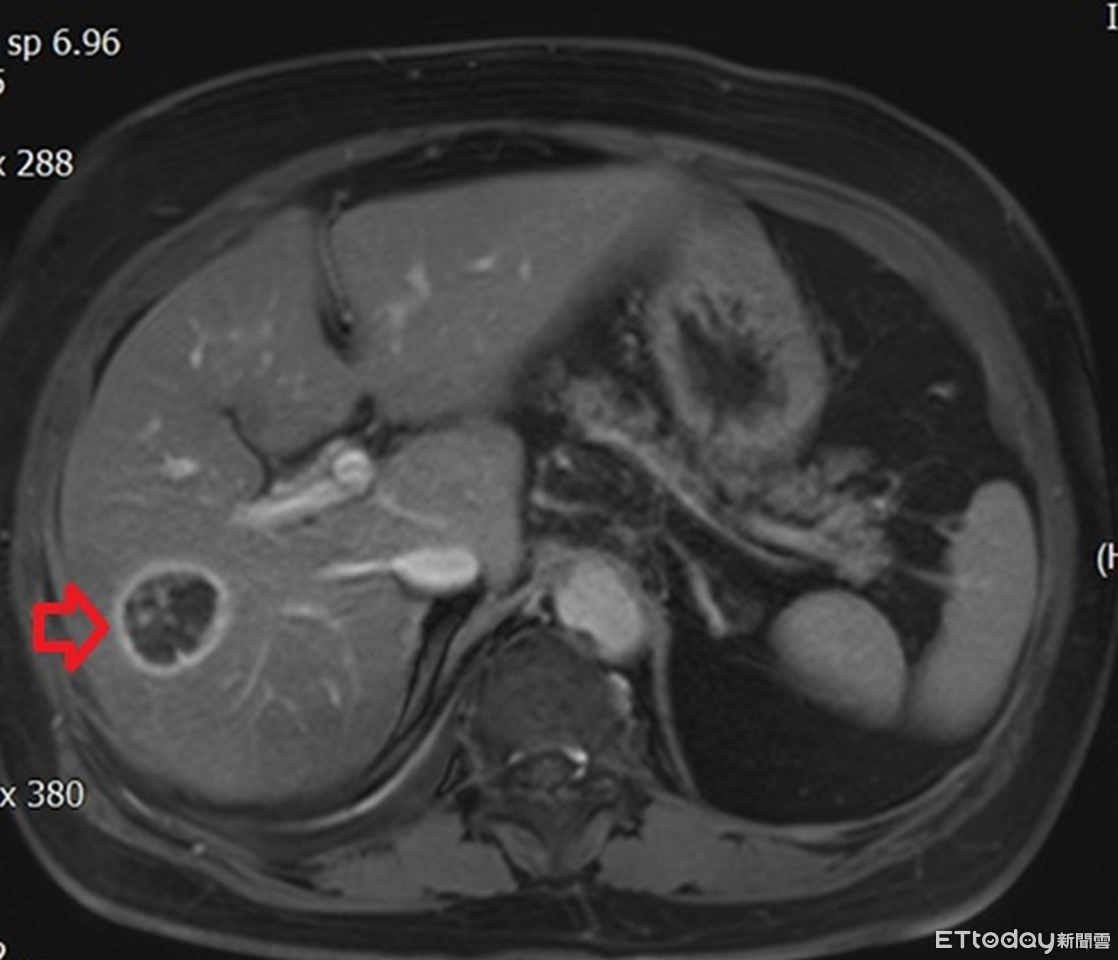

▲年近8旬患者患有多重慢性病,檢查又發現肝癌。(圖/醫師提供,下同)

年近8旬的許奶奶患有慢性肺病、心臟衰竭、糖尿病、高血壓等多種慢性疾病,半年前回診發現肝指數過高,感染科醫師遂安排腹部超音波檢查,結果發現脂肪肝及肝臟一顆約3公分大腫瘤。醫師指出,考量患者肝功能及身體狀況,手術風險高,醫療團隊以腫瘤射頻燒灼術治療,許奶奶也在術後3天平安出院。

肝癌的診斷除了觀察臨床表現外,還需藉由抽血檢查檢驗肝功能狀態,並利用腹部超音波、電腦斷層或核磁造影等相關檢查確認腫瘤型態、大小以及是否有轉移。在手術治療方面,除了傳統開腹手術、微創腹腔鏡或達文西手術外,尚有腫瘤射頻燒灼術的選擇,主要運用於腫瘤小於2至3公分的患者或心肺功能無法負荷麻醉或手術風險較高的病患。